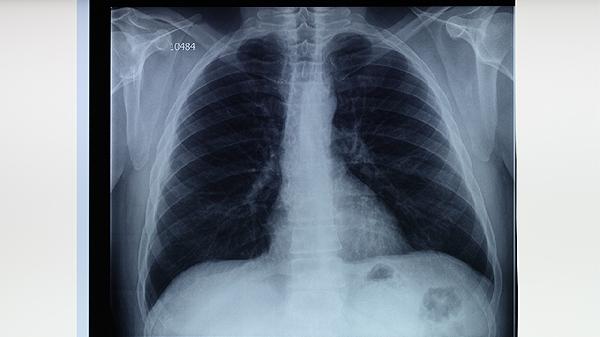

肺結(jié)核治療需遵循早期、聯(lián)合、適量、規(guī)律、全程用藥的原則,主要措施包括規(guī)范使用抗結(jié)核藥物、定期復(fù)查、隔離防護(hù)等。肺結(jié)核是由結(jié)核分枝桿菌感染引起的慢性傳染病,需在醫(yī)生指導(dǎo)下完成6-9個(gè)月的標(biāo)準(zhǔn)療程。

強(qiáng)化期2個(gè)月后需繼續(xù)4-7個(gè)月的鞏固治療。即使癥狀消失,病灶中仍可能存在休眠菌,過早停藥易復(fù)發(fā)。完成全程治療可使治愈率達(dá)到95%以上。治療期間每月需復(fù)查痰涂片、胸部CT,療程結(jié)束后隨訪2年。